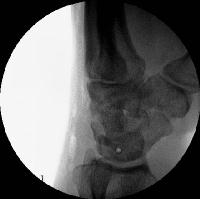

Scapholunate pins and bone anchors - intraoperative fluoroscopy.

Click for larger image